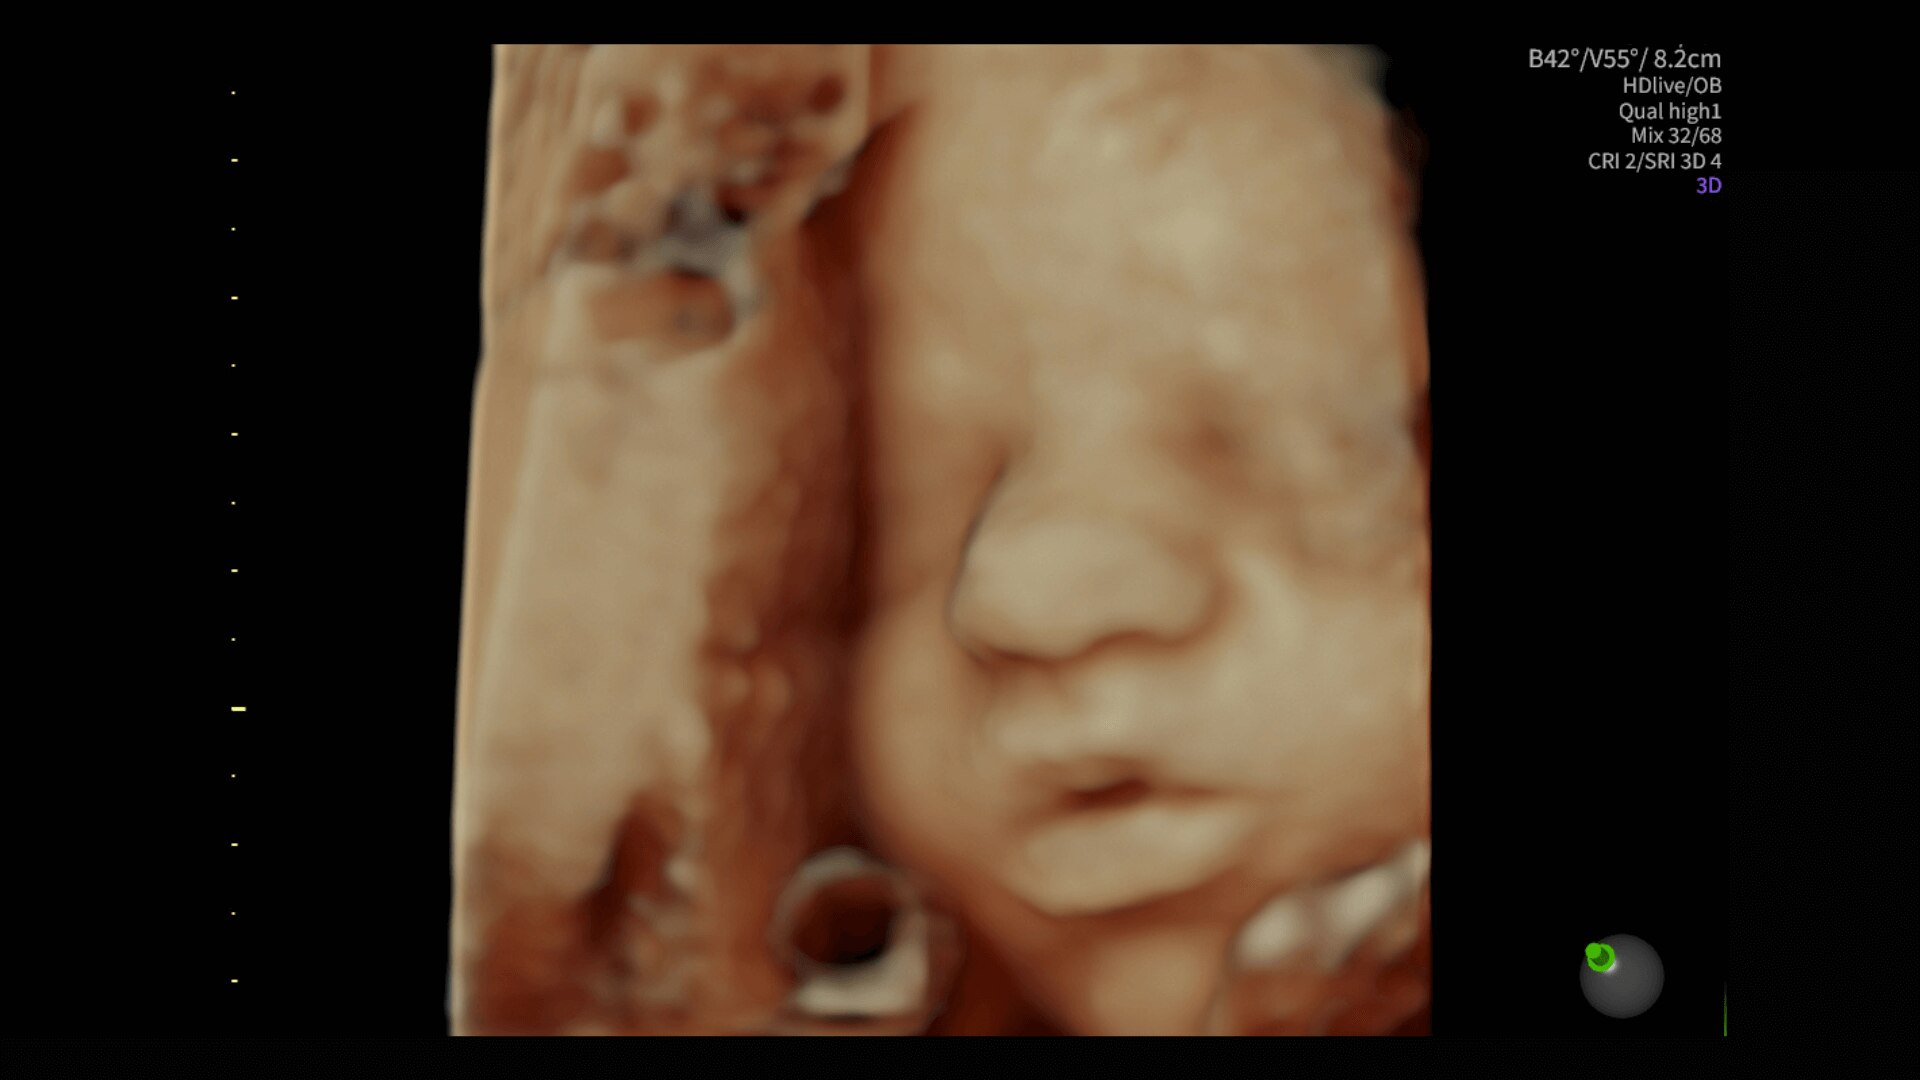

Image quality

Excellent images that are easy to acquire

Image quality is everything in ultrasound

The Voluson Performance 18 delivers high-resolution, detailed imaging with one-touch optimization for effortless scanning—helping you deliver quick, confident answers across a wide range of patient.